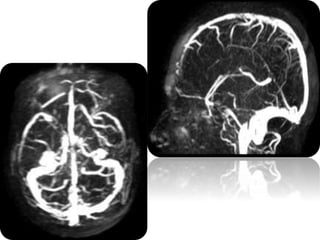

 Posterior reversible encephalopathy syndrome (PRES)

is a clinicoradiological entity

 Posterior reversible encephalopathy syndrome (PRES)

is well recognized because of its typical imaging

appearance, that is involvement of the parieto-

occipital regions

 Enhancement (up to 37%) : cortical, leptomeningeal,

parenchymal or pachymeningeal

 Restricted diffusion (11-26%)

 Hemorrhage (10.5-17.1%) : parenchymal or

subarachnoid

 Altered brain perfusion : regional decreased or

increased, depends on disease time course

 Unilateral hemispheric involvement (2.6%)